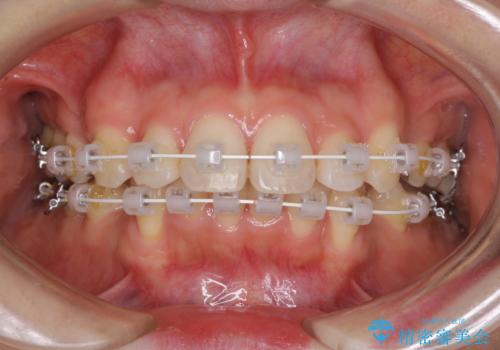

閉じにくい口元 前歯を引っ込める抜歯矯正

- 審美装置

- 上下の出っ歯を気にして来院された患者様です。

口元を積極的に引っ込めるために、上下左右の第一小臼歯を4本抜歯することとしました。

元々ディープバイトのため、スペースを閉じている期間に上下前歯が接触してしまい、治療期間が想定よりも伸びてしまいました。